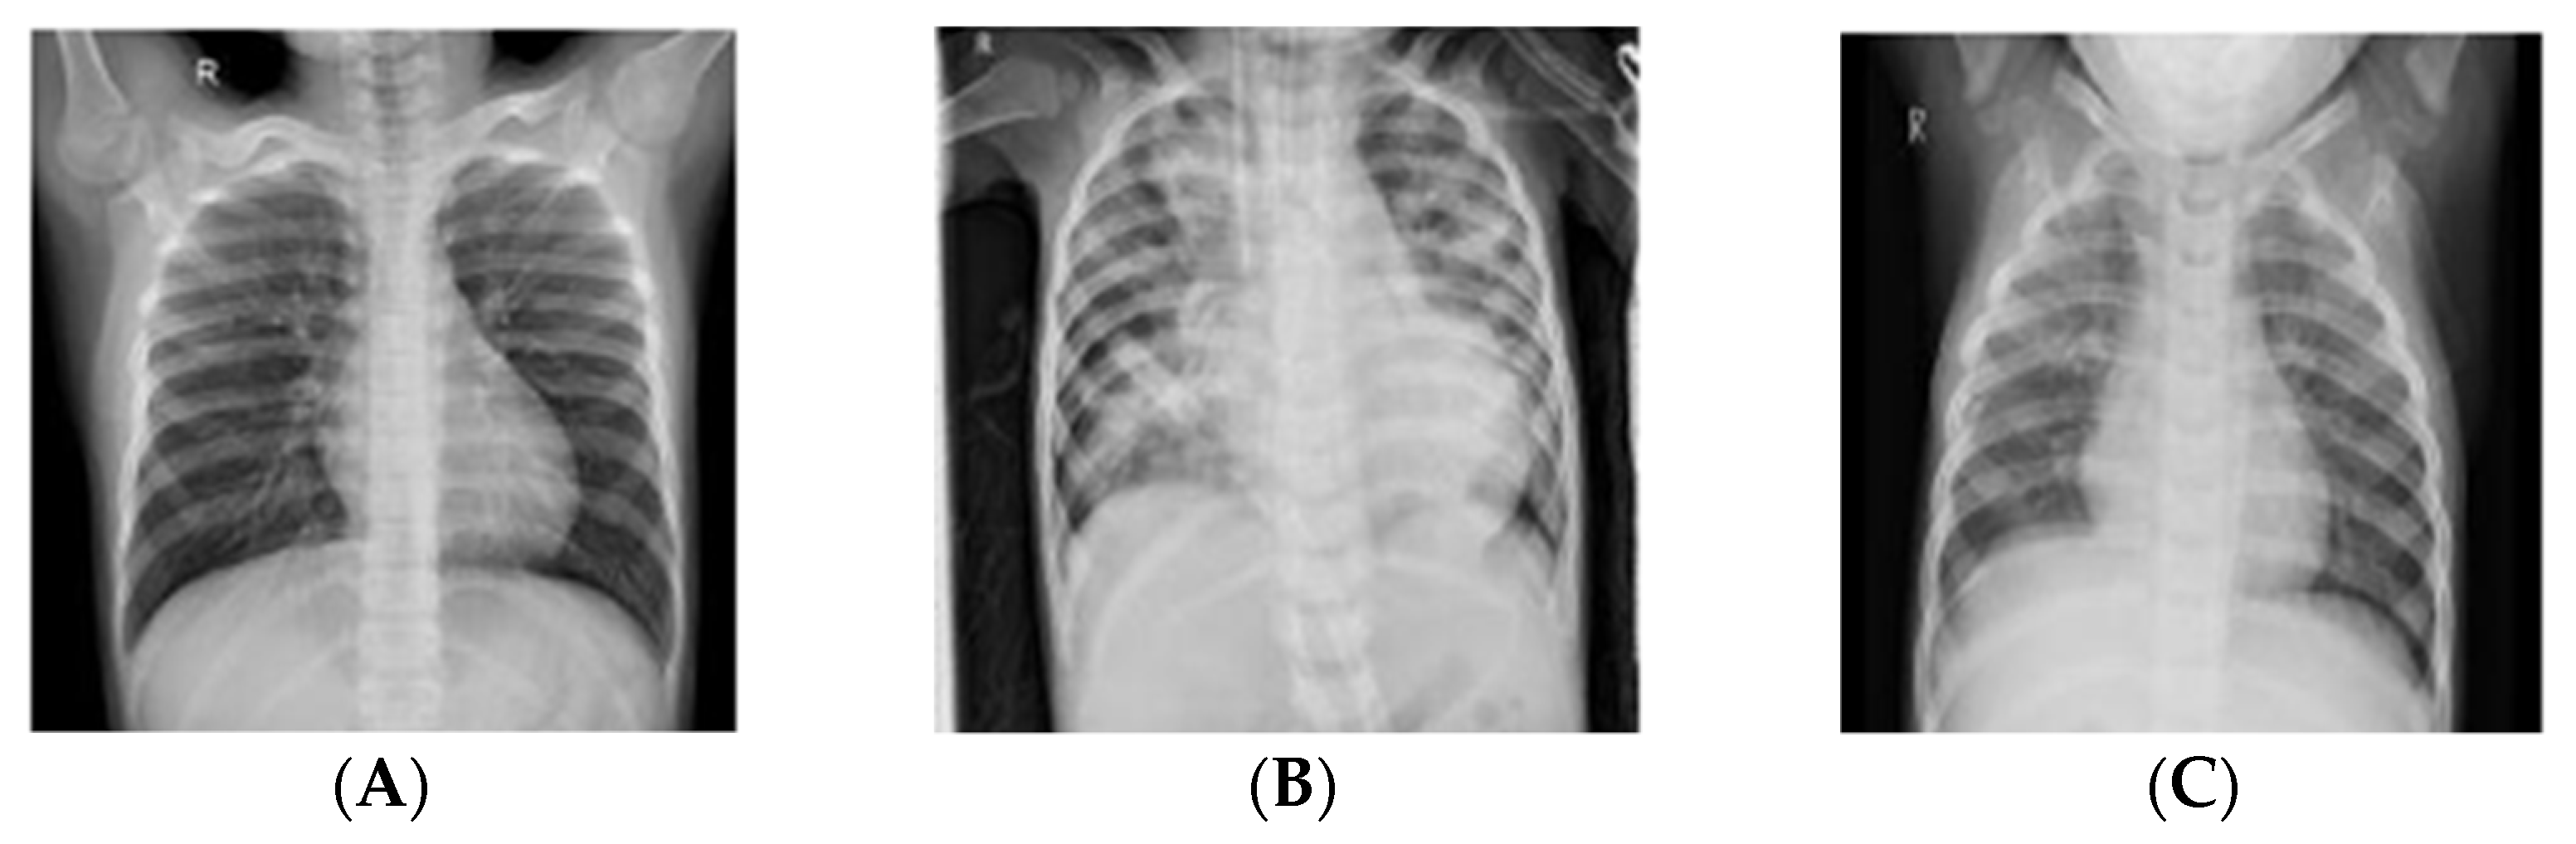

Even though Chest X-rays (CXRs) have a weaker resolution as compared to Magnetic Resonance Imaging (MRI) or Computerized Tomography (CT) scans, they can be used to perform multiple assessments such as cardiomegaly, pneumonia, pneumothorax, and atelectasis. Diagnosing pneumonia using radiographs is highly subjective and depends on the knowledge and expertise of the radiologist. It is easier to diagnose pneumonia using high resolution MRI and CT scans; however, most radiologists use CXRs to perform assessments owing to quicker turn-over and cost effectiveness of the modality. On a typical radiograph, pneumonia is marked by radio-opacities or white spots in the airways, particularly in the alveoli, which indicates the presence of inflammatory exudate. These radiological findings may present a challenge to a novice radiologist, leading to false positives and false negatives owing to the fact that other diseases mimic these signs. Figure 1 shows samples of CXR images that were utilized in this study and classified as normal, bacterial pneumonia, and viral pneumonia from the pediatric group.

Figure 1. Pediatric Chest X-ray images; normal (A), bacterial pneumonia (B), and viral pneumonia (C).